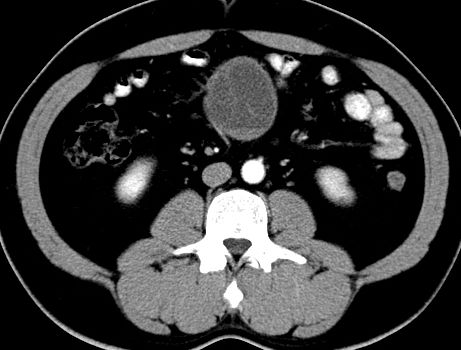

男,48岁,间断性下腹不适1年。

手术探查

:距回盲部28厘米处肠系膜根部可见5*7cm左右包块,质中等硬度,活动度尚可,肝、胆、胰、脾肾未见明显异常。

病理

:(腹腔)

神经鞘瘤

,伴出血、坏死及囊性变,伴淋巴结反应性增生。

免疫组化结果

:sma(-), desmin(-), cd117(-), s-100(+++), nf(-),vimentin(+++).